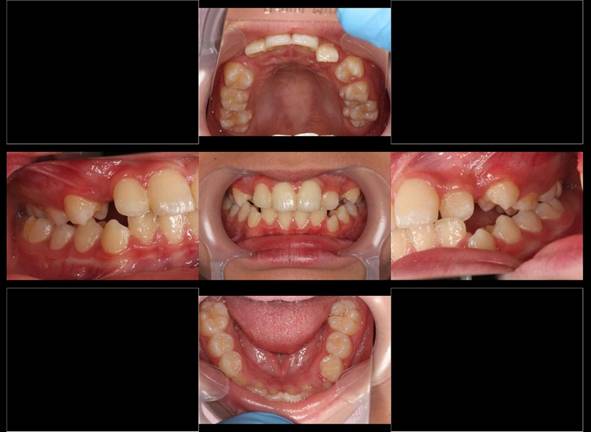

連続抜去法(10歳ごろ犬歯の萌出寸前に第一小臼歯を抜歯する方法です)

左上側切歯の被害はワイヤーを短期間使用しています

5年後 きれいな歯列になっています。 時期によれば小臼歯4本抜歯でここまできれいに並びます